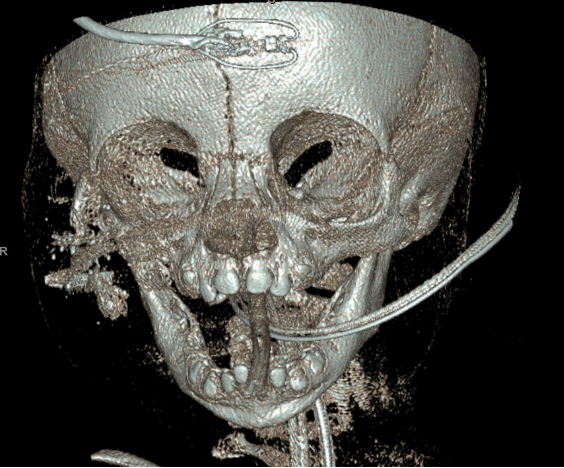

Results: The surgical approach aimed to restore facial symmetry, maintain orbital integrity, and allow for future facial growth without compromising function. A virtual planning session preoperatively allowed accurate measurement of the patient’s defect and fabrication of both a defect model and perfected model using a mirror image of the patient’s unaffected side. Postoperatively, the patient exhibited stable structural support in the orbitozygomatic region with satisfactory aesthetic outcomes. Early follow-up demonstrated adequate healing with no signs of graft rejection or infection. Long-term follow-up will be necessary to monitor facial growth and ensure ongoing stable functional and aesthetic results.

Outcomes: Intraoperative CT scan was taken demonstrating satisfactory position of cadaveric rib segments resulting in re-establishment of the architecture of the zygoma and orbital rims. Early postoperative follow-up demonstrated adequate healing and establishment of zygomatic projection with no signs of graft rejection or infection.

Intraoperative placement of rib allograft implants  Postoperative 3D Reconstruction

Postoperative 3D Reconstruction